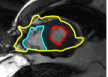

The problem above is a generalization of Horn & Schunck optical flow. Note that solving for the Horn & Schunck optical flow within each region separately does not lead to motions such that at the interface, they have equal normal components (see Figure 1), whereas the solution of (5) to be presented in subsequent sections does. Note that computing Horn & Schunck optical flow in each region requires boundary conditions (and typically they are chosen to be Neumann boundary conditions: and on ). Note that replacing these boundary conditions with the boundary constraint (6) does not specify a unique solution. Also, while Horn & Schunck optical flow computed on the whole domain naturally gives a globally smooth motion, which by default satisfies matching normals at the interface, this is not natural for the ventricles / myocardium, where different motions exist in the regions (see Figure 2), and the motions should not be smoothed across the regions.

![]() |

| image + boundary | next image | within region optical flow | our method |